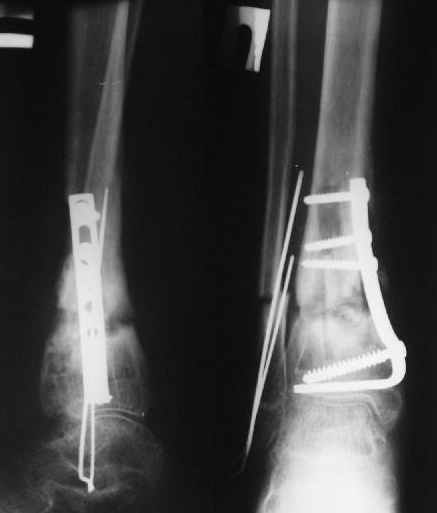

Операции: 1 Клиновидная резекция на вершине деформации м\берцовой кости.

2 Тугоподвижный ложный сустав н\3 б\берцовой кости. Рубцы выполняющие пространство между отломками, канал проксимального отломка иссечены.

Одномоментное устранение деформации, остеосинтез Г-образной пластиной.

Пластика по Хахутову.

Заживление проксимальной части раны вторичным натяжением без нагноения. Рана зажила. Спицы удалены через 1,5 недели после операции.